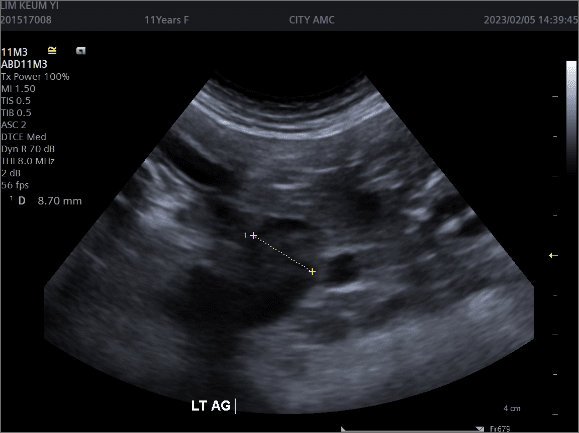

부신에서 코르티솔이 과다하게 분비되어 발생하는 질환.

뇌하수체 종양에 의해 부신이 자극받는 경우가 가장 흔함.